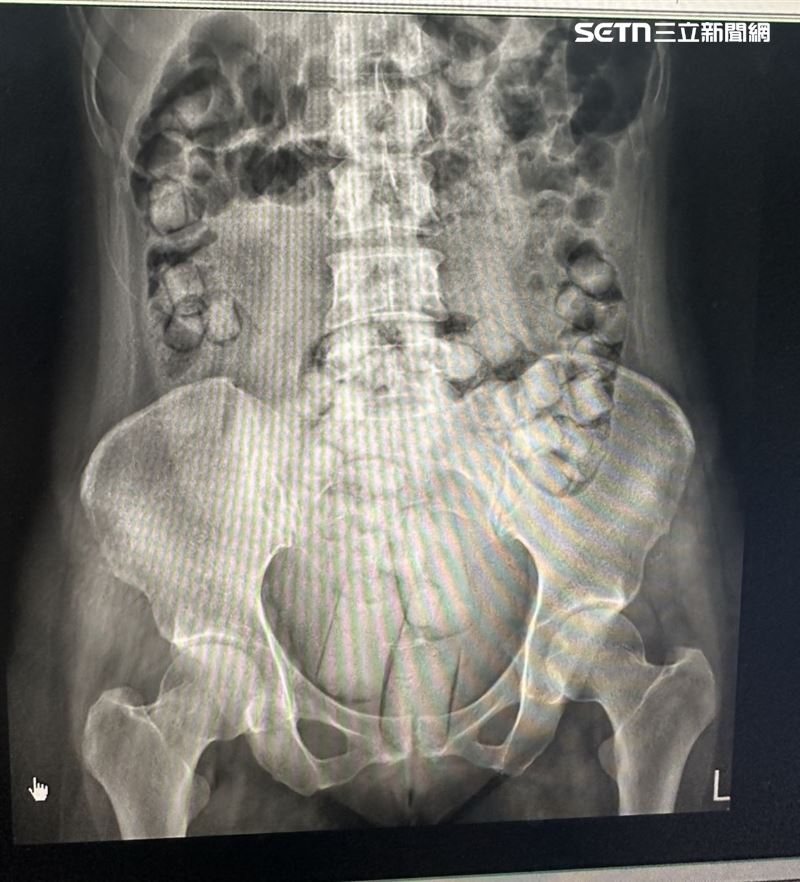

二人於同日下午從小港機場入境時,因海巡署已提前掌握情資,立即將二人帶往小港醫院照X光,在二人體內發現大量塊狀物體,經醫師開瀉藥排出後,所有塊狀物均檢測出海洛因反應,二人當場被警方逮捕,後續被彰化地檢署依違反毒品危害防制條例起訴。